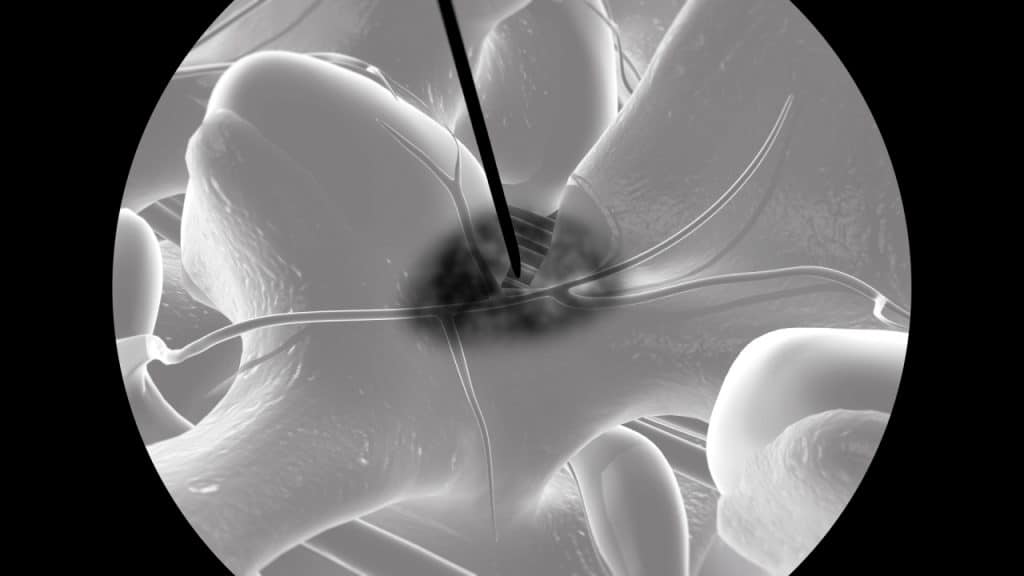

Die medialen Nervenäste sind sehr kleine Nerven, die Schmerzsignale von den Facettengelenken zum Gehirn transportieren. Jedes Gelenk empfängt Signale von einem medialen Nervenast, der von zwei verschiedenen Ebenen ausgeht.

Die Infiltration des medialen Nervenastes mit einem Lokalanästhetikum ist eine hauptsächlich diagnostische Injektion unter Bildwandlerkontrolle, die zur Lokalisierung eines schmerzenden Facettengelenks dient. Dabei sollen beide mediale Nervenäste des Gelenks betäubt werden. Die Diagnose wird bestätigt, wenn die Injektion eine deutliche vorübergehende Schmerzlinderung bewirkt. In diesem Fall kommt als nächste Therapieoption die Radiofrequenzdenervation der Facettengelenke in Betracht.